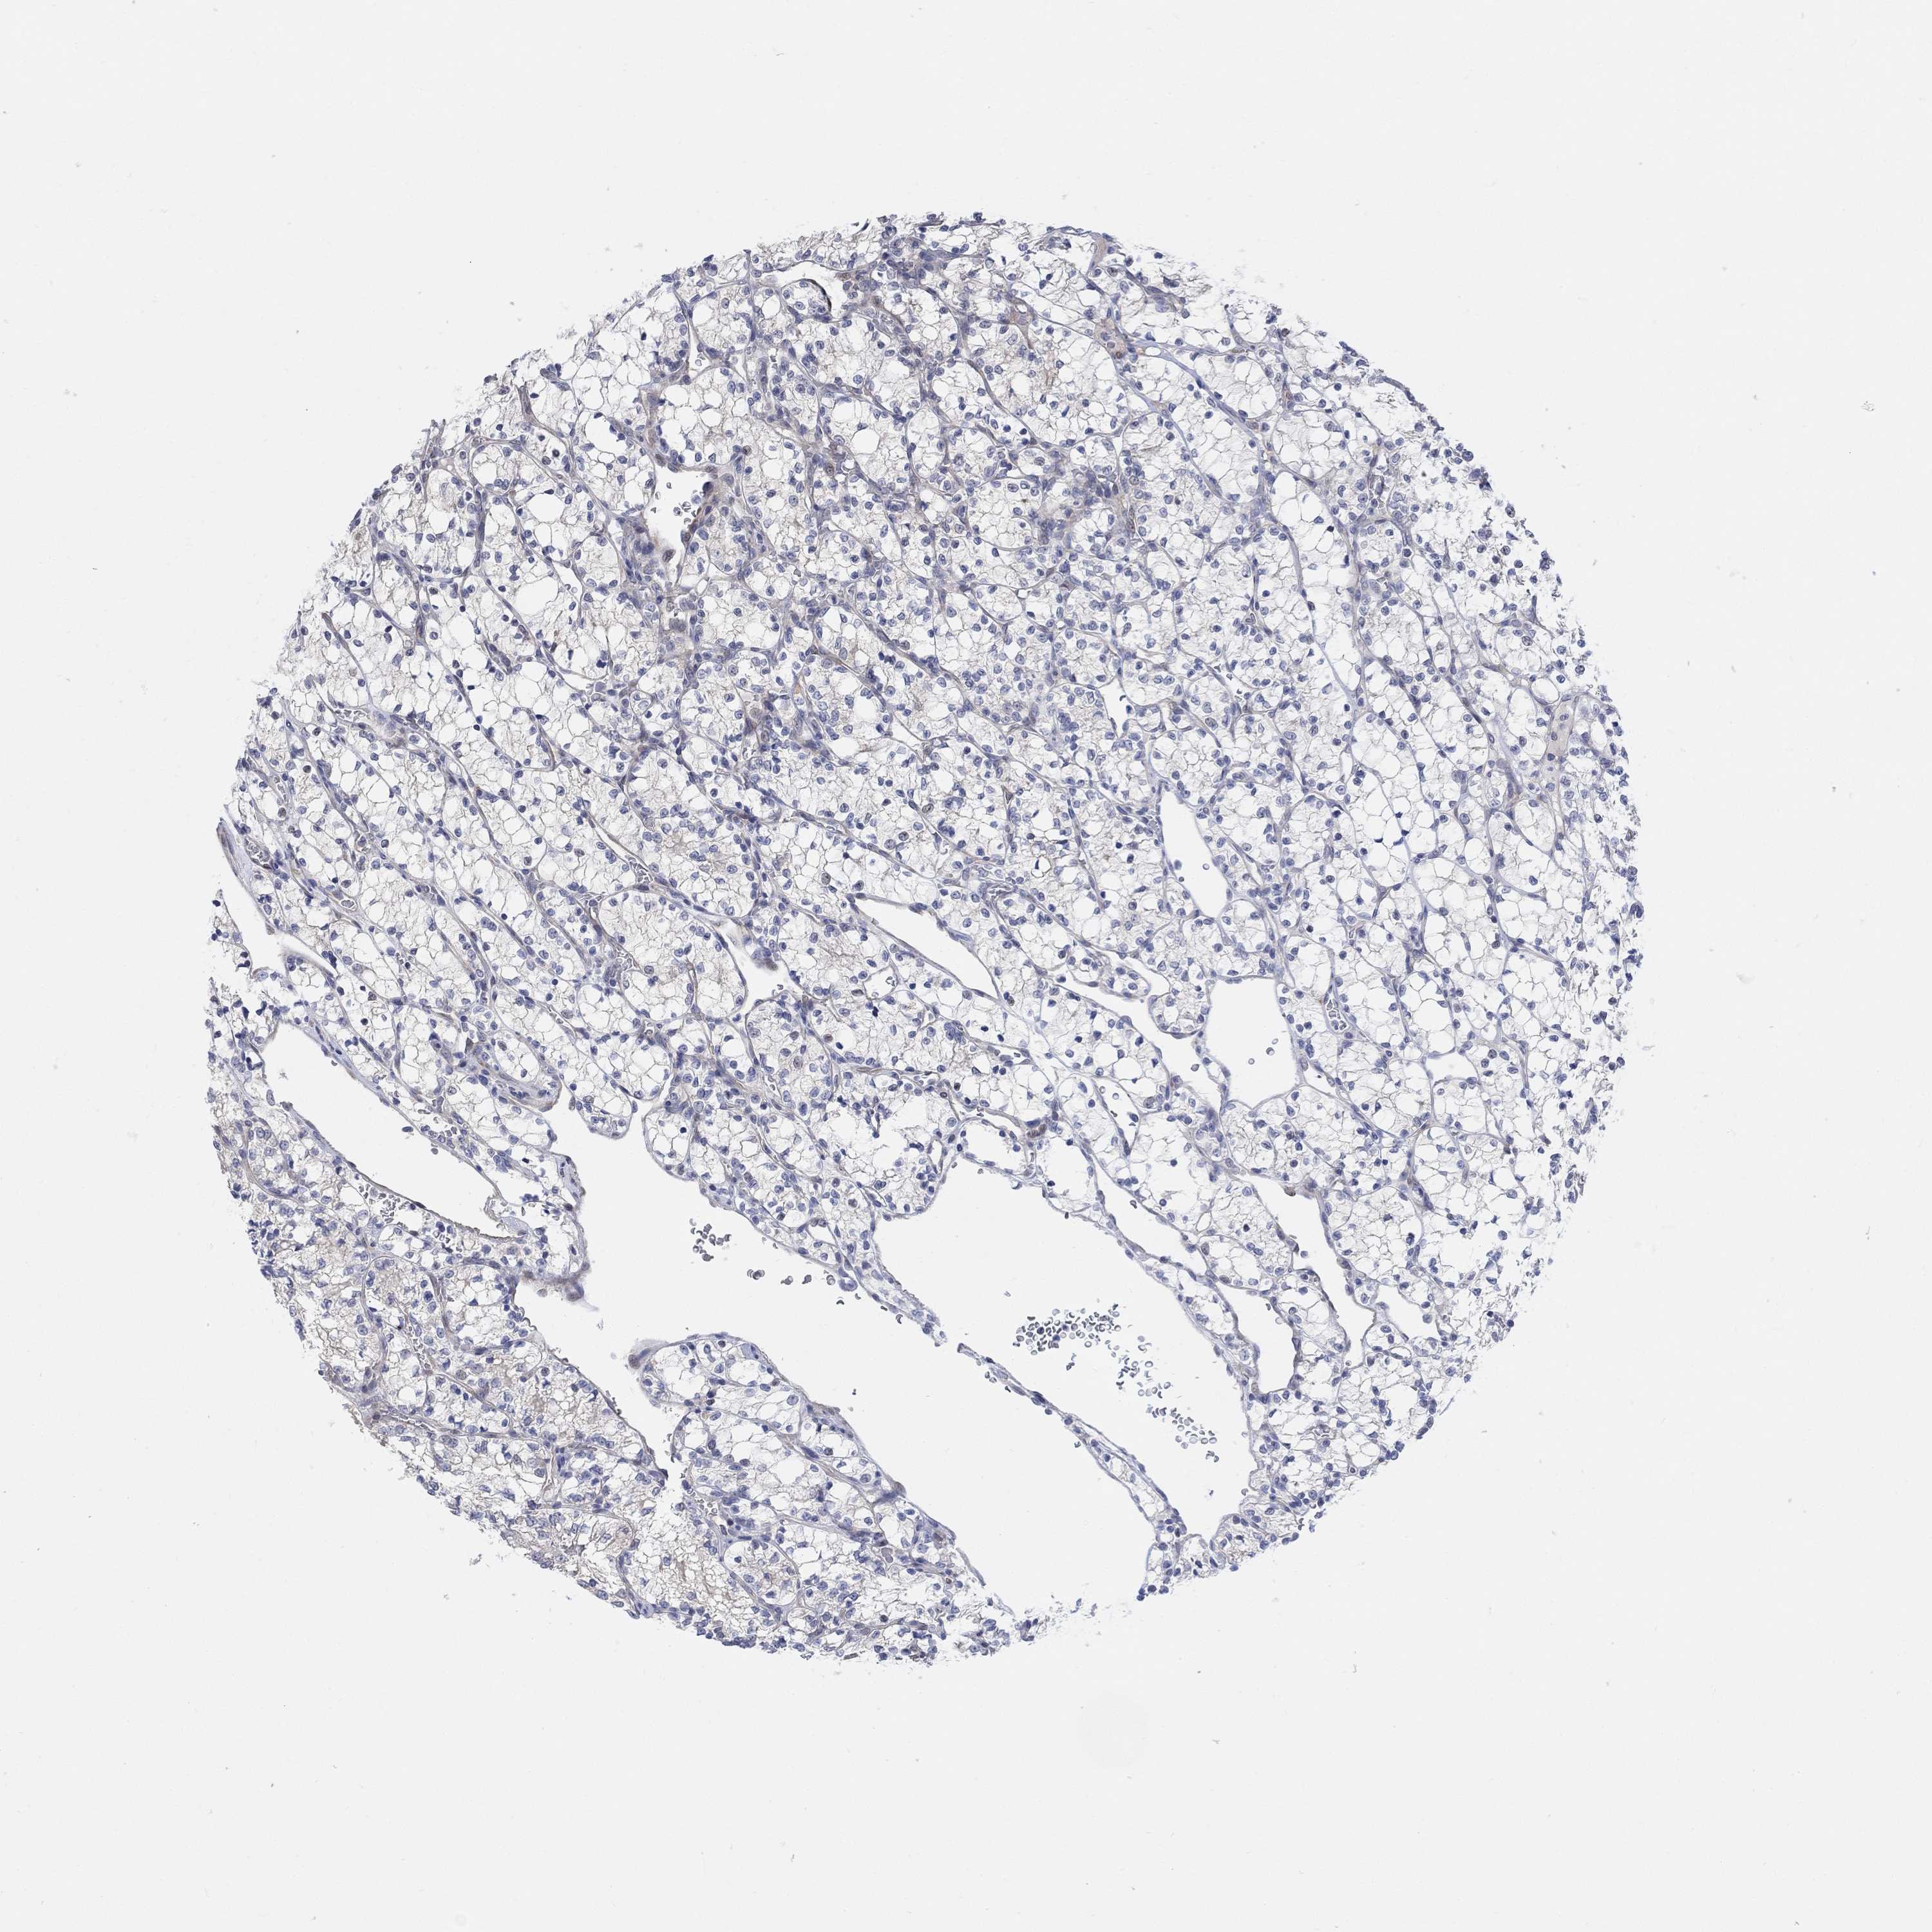

KIDNEY RENAL CLEAR CELL CARCINOMA (TCGA) - Interactive survival scatter ploti

The Survival Scatter plot shows the clinical status (i.e. dead or alive) for all individuals in the patient cohort, based on the same data that underlies the corresponding Kaplan-Meier plots. Patients that are alive at last time for follow-up are shown in blue and patients who have died during the study are shown in red.

CNTF is not prognostic in Kidney Renal Clear Cell Carcinoma (TCGA)